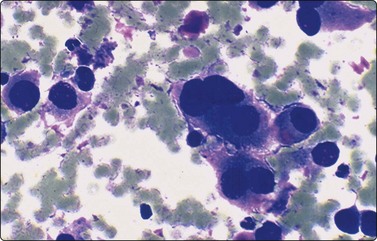

Neuroblastoma usually forms a well-defined solid tumor <10 cm in size with hemorrhage and extentive necrosis. The FNA usually yields hypercellular smears with predominant individually scattered small anaplastic cells, showing prominent nuclear molding.27,41,42 The prototypical neuroblastic cells have high nuclear to cytoplasmic ratios with single nuclei that are oval to slightly irregular in shape containing evenly dispersed granular chromatin (salt and pepper) and small to inconspicuous nucleoli (Fig. 17.1). Small round cells are arranged in moderately or well-formed Homer-Wright rosettes surrounding centrally located neuropil, which stains pink or blue–gray in Giemsa-stained smears. The presence of Homer-Wright rosettes is diagnostic but not present in all cases (Fig. 17.2). Neuropil, either associated with the rosettes or present in the smear background, is the most helpful cytologic feature for rendering a definitive cytologic diagnosis of neuroblastoma.34 Neuropil consists of a fibrillary tangle of neuritic processes with or without associated neuroblastic cells (Fig. 17.3). Mitotic–karyorrhectic cells and calcifications can occasionally be recognized in aspirate smears. Larger differentiating neuroblasts with moderate amounts of cytoplasm and binucleated to multinucleated ganglion cells can also be present in the smear. Some neuroblastomas may undergo different grades of maturation, forming ganglioneuroblastoma or ganglioneuroma. In ganglioneuroblastoma, the smear is pleomorphic with prominent anisonucleosis and abundant neuropil background but without ganglion cells, while ganglioneuroma demonstrates characteristic ganglion cells (Fig. 17.4).27,42

image

Fig. 17.3 Neuroblastoma

Medium power of aspirate smear containing neuroblastic cells associated with fibrillary to granular background neuropil (Pap, ×200).